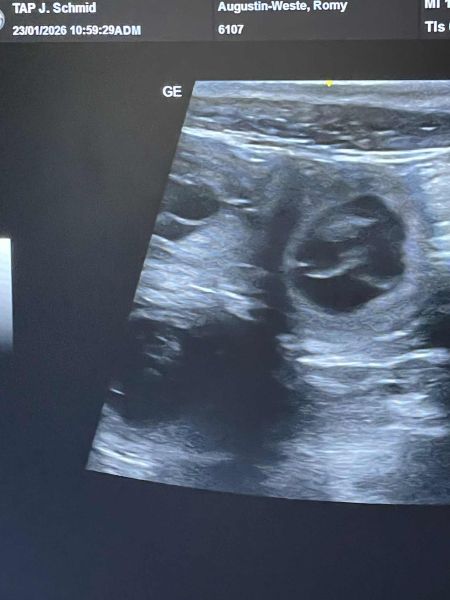

Die Verpaarung Romy x Juno war erfolgreich, wie man am Ultraschallbild erkennen kann.

Wir freuen uns sehr und erwarten unsere Welpen am 15. März 2025 +/-